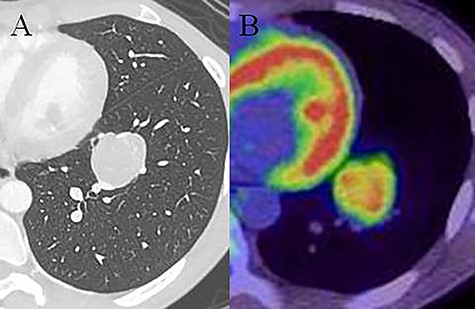

A 20-year-old man was referred to our hospital because of a tumor in his left lung that was discovered on chest radiographs. Chest computed tomography (CT) showed a 35-mm nodule in the lower lobe of the left lung (Fig. 1a). Fluorodeoxyglucose-positron emission tomography (FDG-PET) showed high accumulation in the nodule (maximum standard uptake value (SUVmax): 5.9; Fig. 1b). There was no accumulation in the hilar and mediastinal lymph nodes. Bronchoscopic examination and cryobiopsy were performed, which indicated suspicious for sclerosing pneumocytoma. To confirm the diagnosis and for treatment, we performed video-assisted thoracoscopic surgery (VATS). Intraoperative frozen pathological examination revealed that there were no metastases in the segmental lymph nodes (No. 13). Then, we performed basal segmentectomy considering curability and the preservation of pulmonary function. The operating time was 154 min and blood loss was 30 ml. However, the postoperative pathological diagnosis revealed lymph node metastasis in the segmental lymph nodes. Considering the possibility of remaining lymph node metastases, we performed additional resection of segment 6 (completion lower lobectomy) and hilar and mediastinal lymph node dissection by VATS, 2 weeks after the first surgery. The operating time was 266 min and blood loss was 200 ml. Hilar adhesions were moderate, and these were carefully dissected to avoid injuring the pulmonary artery. Then, the pulmonary artery was safely cut using a stapler. The bronchus of the left lower lobe was cut at the root using a stapler, followed by radical hilar lymph node dissection. The patient’s postoperative course was favorable, and he was discharged 13 days after the second surgery. Pathological examination of the second resected specimen revealed lymph node metastases in the interlobar (No. 11) and mediastinal lymph nodes (No. 4 L, 7 lymph nodes; Fig. 2). Six months after the surgery, he was alive without no recurrence or metastasis.

Chest computed tomography (CT) showing a 35-mm nodule in the lower lobe of the left lung (A). Fluorodeoxyglucose-positron emission tomography (FDG-PET) showing high accumulation in the nodule (SUVmax: 5.9; B).